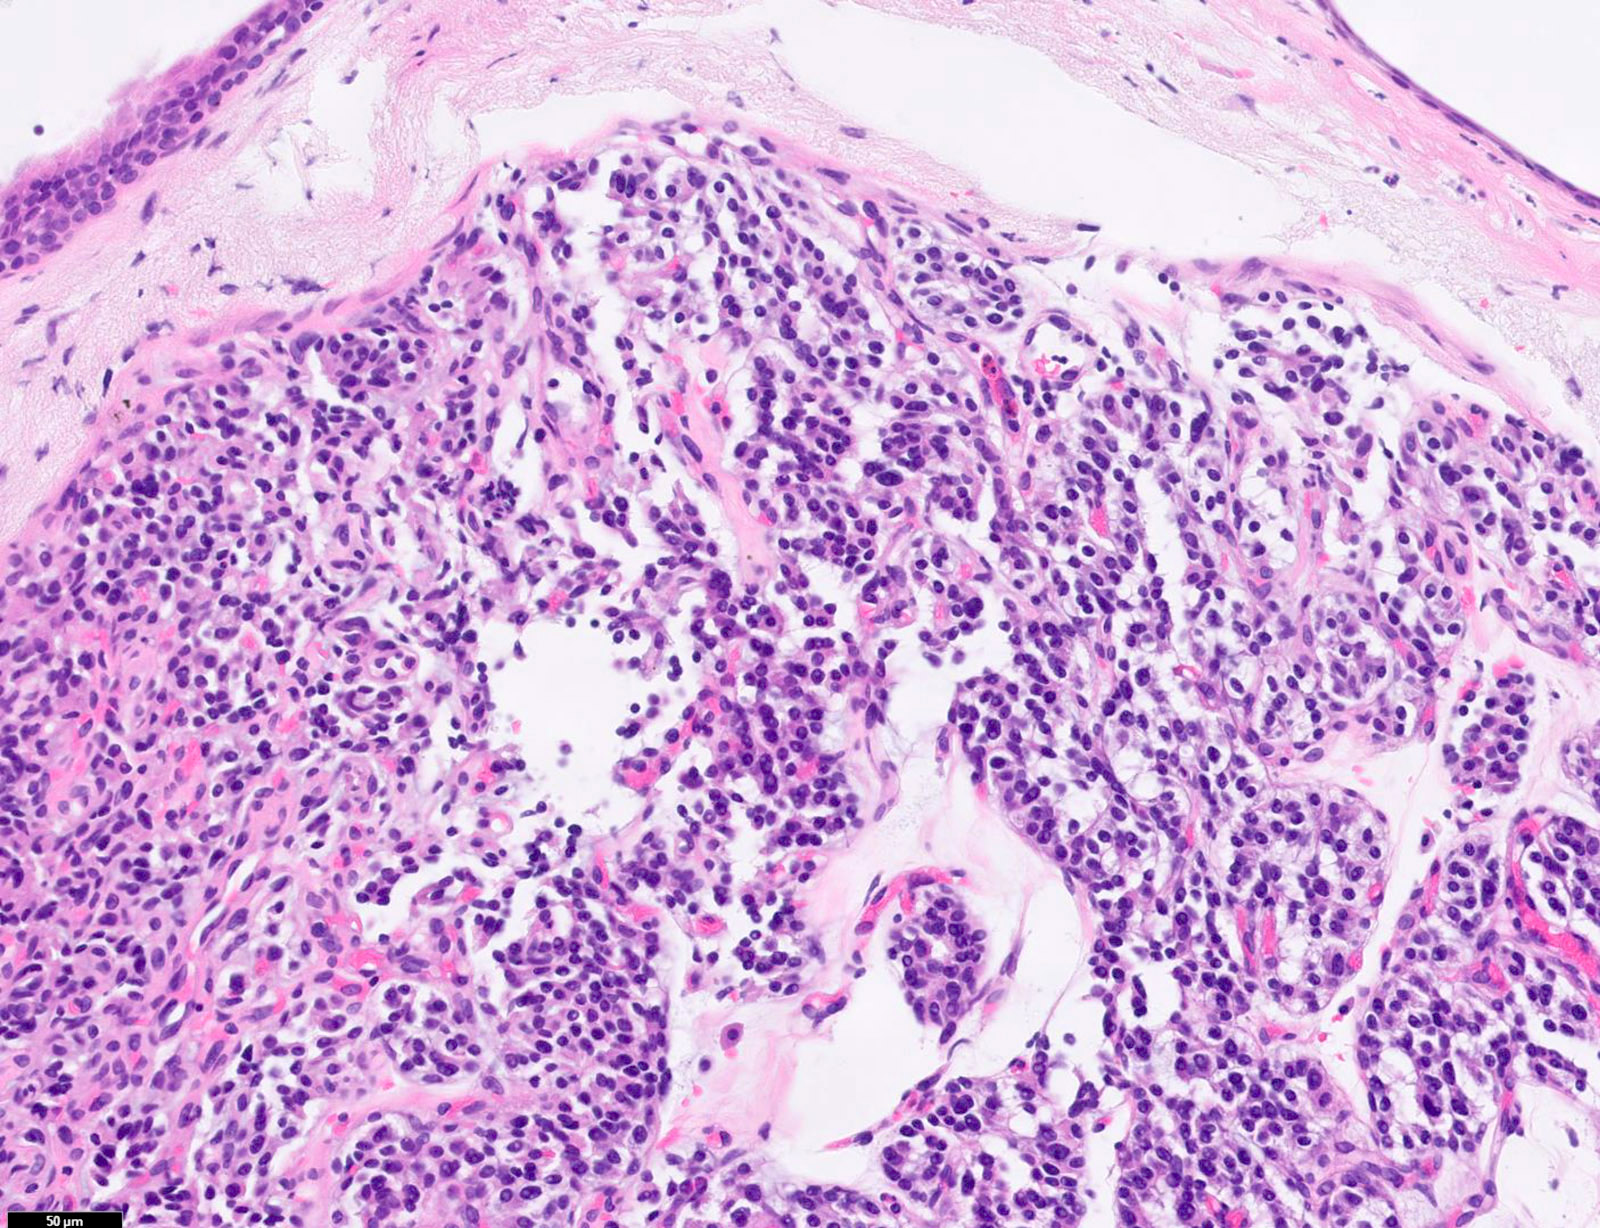

Microscopic (histologic) description

- Diagnostic criteria

- Neuroendocrine tumor with size ≥ 5 mm with < 2 mitoses/2 mm2 and absence of necrosis

- Neuroendocrine growth pattern (organoid, trabecular, rosette formation, nested) or pseudoglandular, follicular and papillary growth

- Tumor cells are uniform with a polygonal shape, round to oval nuclei with salt and pepper chromatin as well as inconspicuous nucleoli and moderate to abundant eosinophilic cytoplasm

- Spindle cells and clear cell features can be seen

- Stroma is fine and highly vascularized; hyalinization, cartilage or bone formation are possible

- Reference: Curr Oncol 2018;25:S86

Microscopic (histologic) images

Contributed by Philippe Joubert, M.D., Ph.D., Jijgee Munkhdelger, M.D., Ph.D. and Andrey Bychkov, M.D., Ph.D.

A. CDX2 is usually negative in the lung and is useful to differentiate from a metastasis of an intestinal origin. The image shows a tumor with a trabecular pattern and pseudorosettes. The stroma is highly vascularized. Tumor cells are monotonous with scant to moderate eosinophilic cytoplasm. Nuclei are round to oval with salt and pepper chromatin and inconspicuous nucleoli. No mitoses are seen. These features are consistent with a typical carcinoid lung tumor.